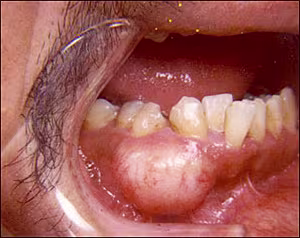

History of Present Illness The patient reported that the lesion had been enlarging slowly for the past 21 years. The mass was not tender and the patient did not recall any history of trauma. No other information was available. Medical History The patient’s medical history was unremarkable. He denied alcohol and tobacco use. Clinical Findings The clinical exam revealed a 3×2 cm “bony hard” swelling of the right mandible buccal to #27 and #28. The overlying mucosa was intact and no lingual extension was noted (Figure 1). The remainder of the oral cavity was within normal limits.

Figure 1. Firm, nonulcerated mass of the right mandibular gingiva.